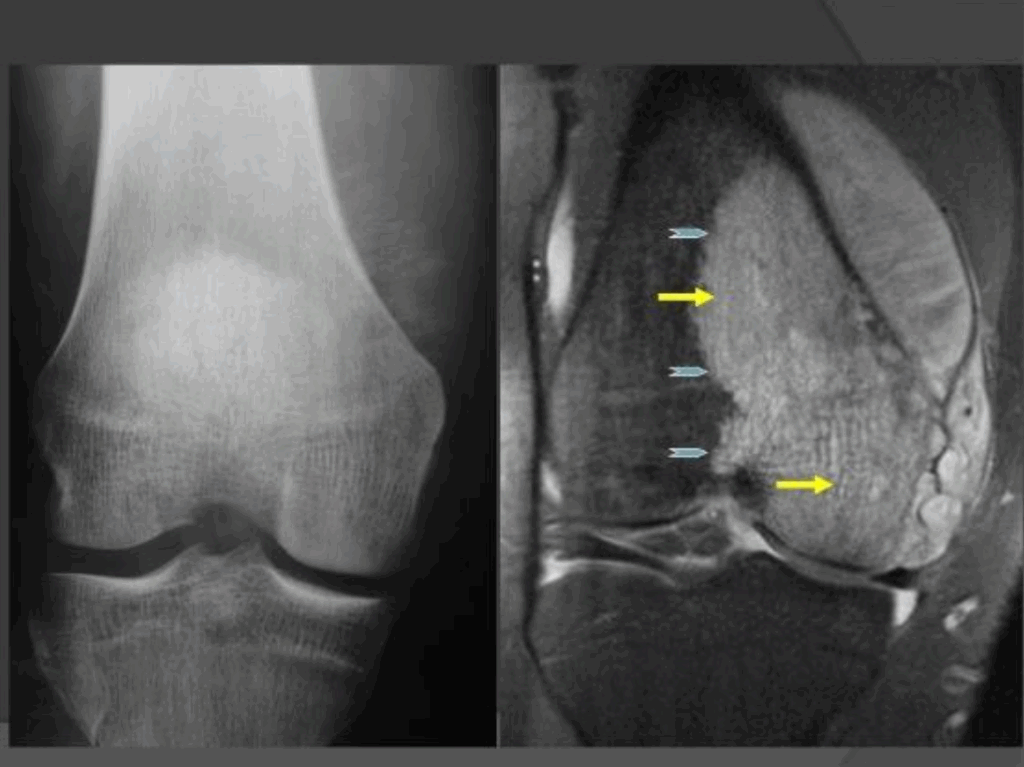

5. OCMR. Sandrine Chilloh